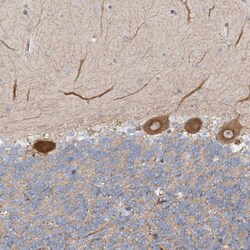

Invitrogen™ FGF19 Polyclonal Antibody

Brand: Invitrogen™ PA5111069

| Immunohistochemistry (Paraffin) | |